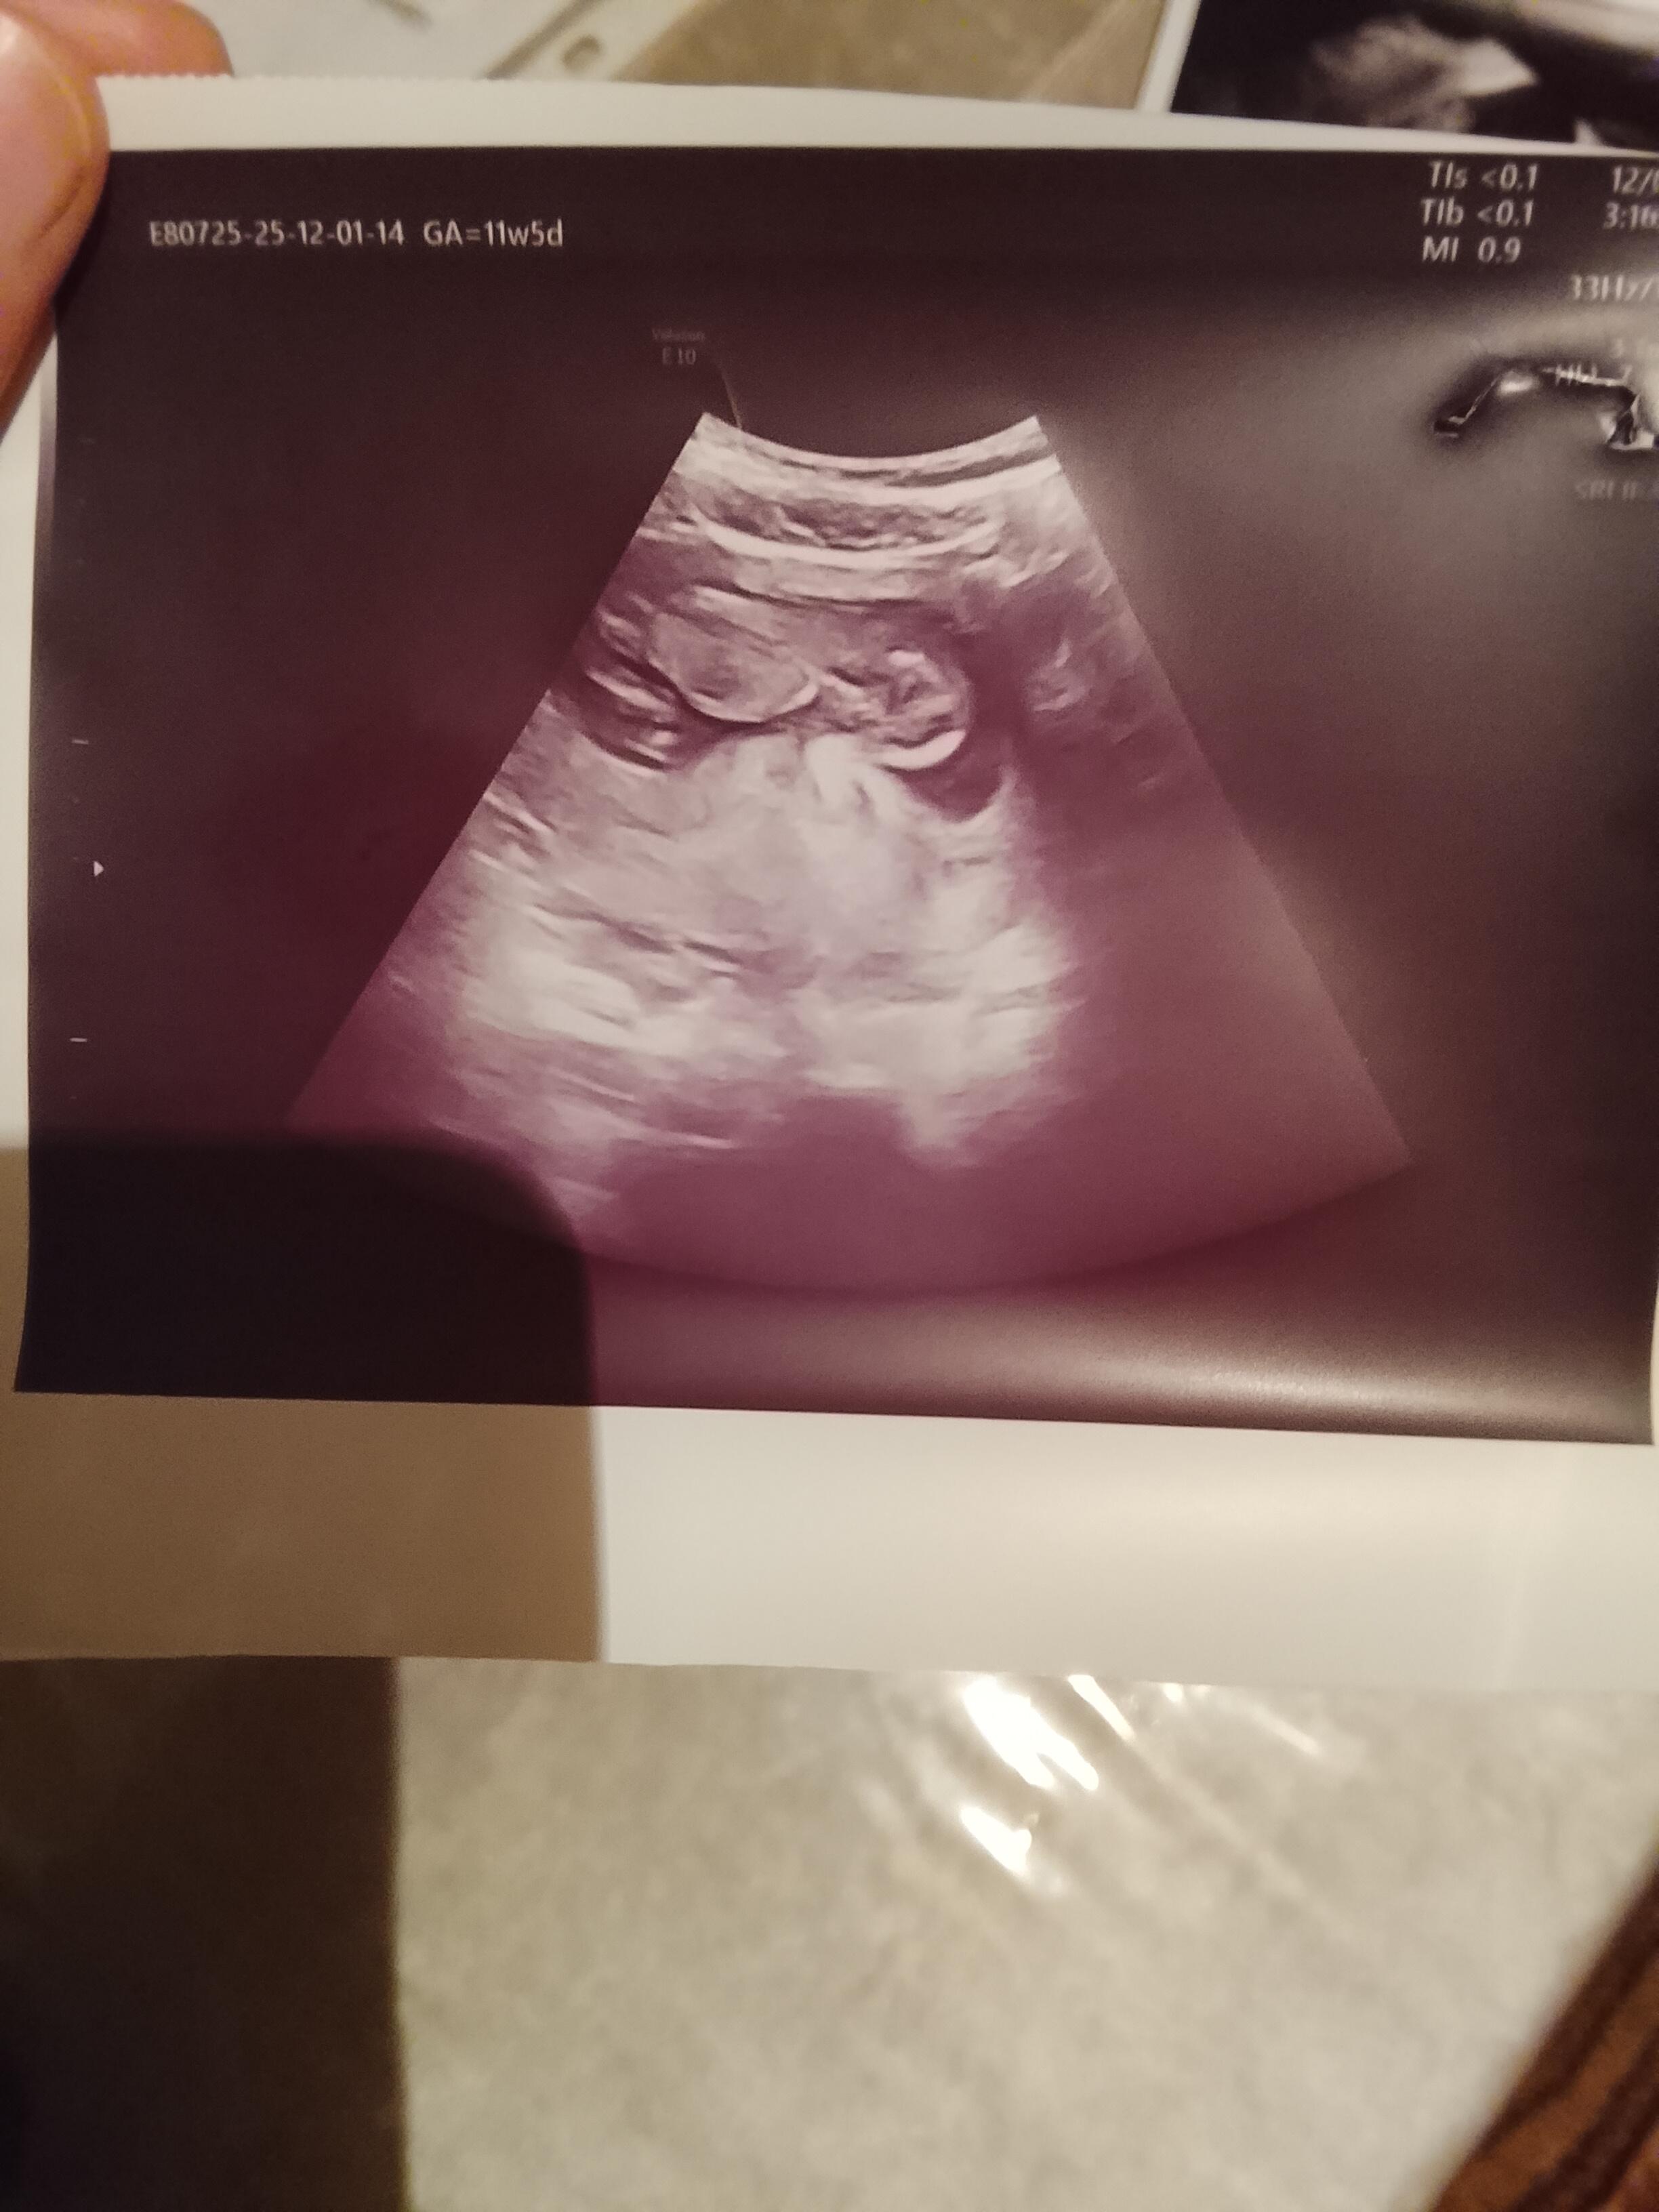

At cnm kaç haftalık oldu

Attımm bakar mısınızzz

Kız bence ya

Erkek gibi duruyo canim Allah bilir yine de boylu boyuna da yatiyo maaşallah Rabbim sağlıklı sıhhatli kucagina almak nasip etsin insallah canım

Erkek bebiş kuzum

Erkek gibi geldi bana da hayırlısını versin rabbim insallah canim allah sag salim sağlıklı bir sekilde kucagina almak nasip etsin insallah